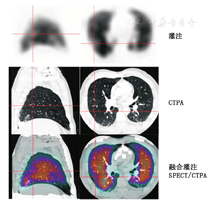

SPECT显像数据可进行更高级的数据处理。首先,通过扣除之前肺通气显像中残留的本底放射性,以进一步增强肺灌注SPECT显像中的放射性缺损对比度[12,30]。其次,通过测定基于像素的V/Q比值可从SPECT数据中生成比值图。这些图像有助于撰写诊断报告,且能改善放射性缺损的定位和程度的显示(图1)[30]。另一项图像处理技术是V/Q比值的客观定量,已证实其能增加诊断准确性,减少诊断不明确数量[31,32]。

随着SPECT/CT的发展,将CT扫描的解剖信息与SPECT显像的功能信息进行融合已成为可能。肺V/Q SPECT显像联合CT扫描,甚至可以采用低剂量CT扫描来降低患者辐射剂量,以充分发挥每种显像模式的优势。肺栓塞以外的病变(如放疗后改变、肺气肿、肿瘤或纵隔淋巴结肿大等病变引起的外周血管受压)造成的V/Q不匹配也可被SPECT/CT显像发现(图2)[17]。另外,SPECT/CT有助于确定非栓塞病因所致的匹配改变,如肺炎、肺脓肿、胸膜或心包积液、肿瘤和肺梗死(图3)[3,9,47]。因此,SPECT/CT融合显像可通过明确引起灌注缺损的原因而提高肺V/Q显像的特异性[18,52]。肺V/Q SPECT/CT显像能通过单次显像过程为肺栓塞探测提供较高灵敏度和特异性的诊断,这也有助于鉴别导致胸痛和呼吸困难的各种其他疾病。

建议肺V/Q SPECT/CT显像与SPECT显像一样按照欧洲核医学协会的指南发报告。尽管这些指南没有专门叙述融合显像,但CT部分的加入可能有助于对肺V/Q SPECT显像进行更恰当的判断。CT可提供患者的解剖信息,包括肺和肺段边界、叶间裂、大血管位置和任何与之相关的实质性病变(图4)。叶间裂位置值得注意,因为在肺灌注SPECT显像上能见到1条与之对应的线形减低,而在肺通气显像上程度低一些。任何V/Q匹配改变的部位都值得注意,因为继发于肺栓塞的实质性改变常发生在缺损外围,而炎性病变所致的病变常见于邻近缺损处[55]。

3.肺V/Q SPECT和CTPA联合显像。结构和功能联合显像的另一选择是将肺灌注SPECT显像与诊断性CTPA融合,这可在同一融合显像仪器上完成或在另一CT扫描后通过软件完成(图6)[58]。尽管这种方法需要合适的软件和专业操作者,但其对特定患者有价值,且利用CTPA能更好地引导放射科报告医师,观察到可疑的栓塞部位[59]。